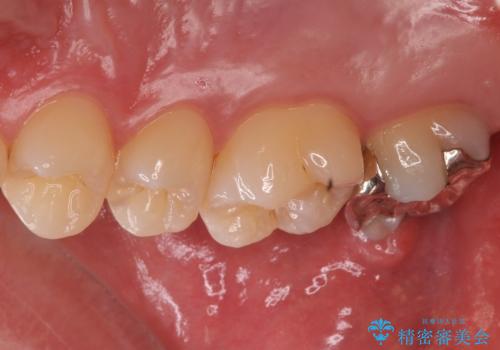

銀歯をなくしたい ジルコニアクラウンでの修復

- 銀歯を白くしたいとのことで来院されました。

歯を覆っている銀の詰め物の面積が広く、セラミックで同じ形態にすると強度に不安が残るため被せ物での修復処置を行っていきます。

- 右上7 仮歯+ジルコニアクラウン:11,000円+121,000円費用は治療当時の料金となります